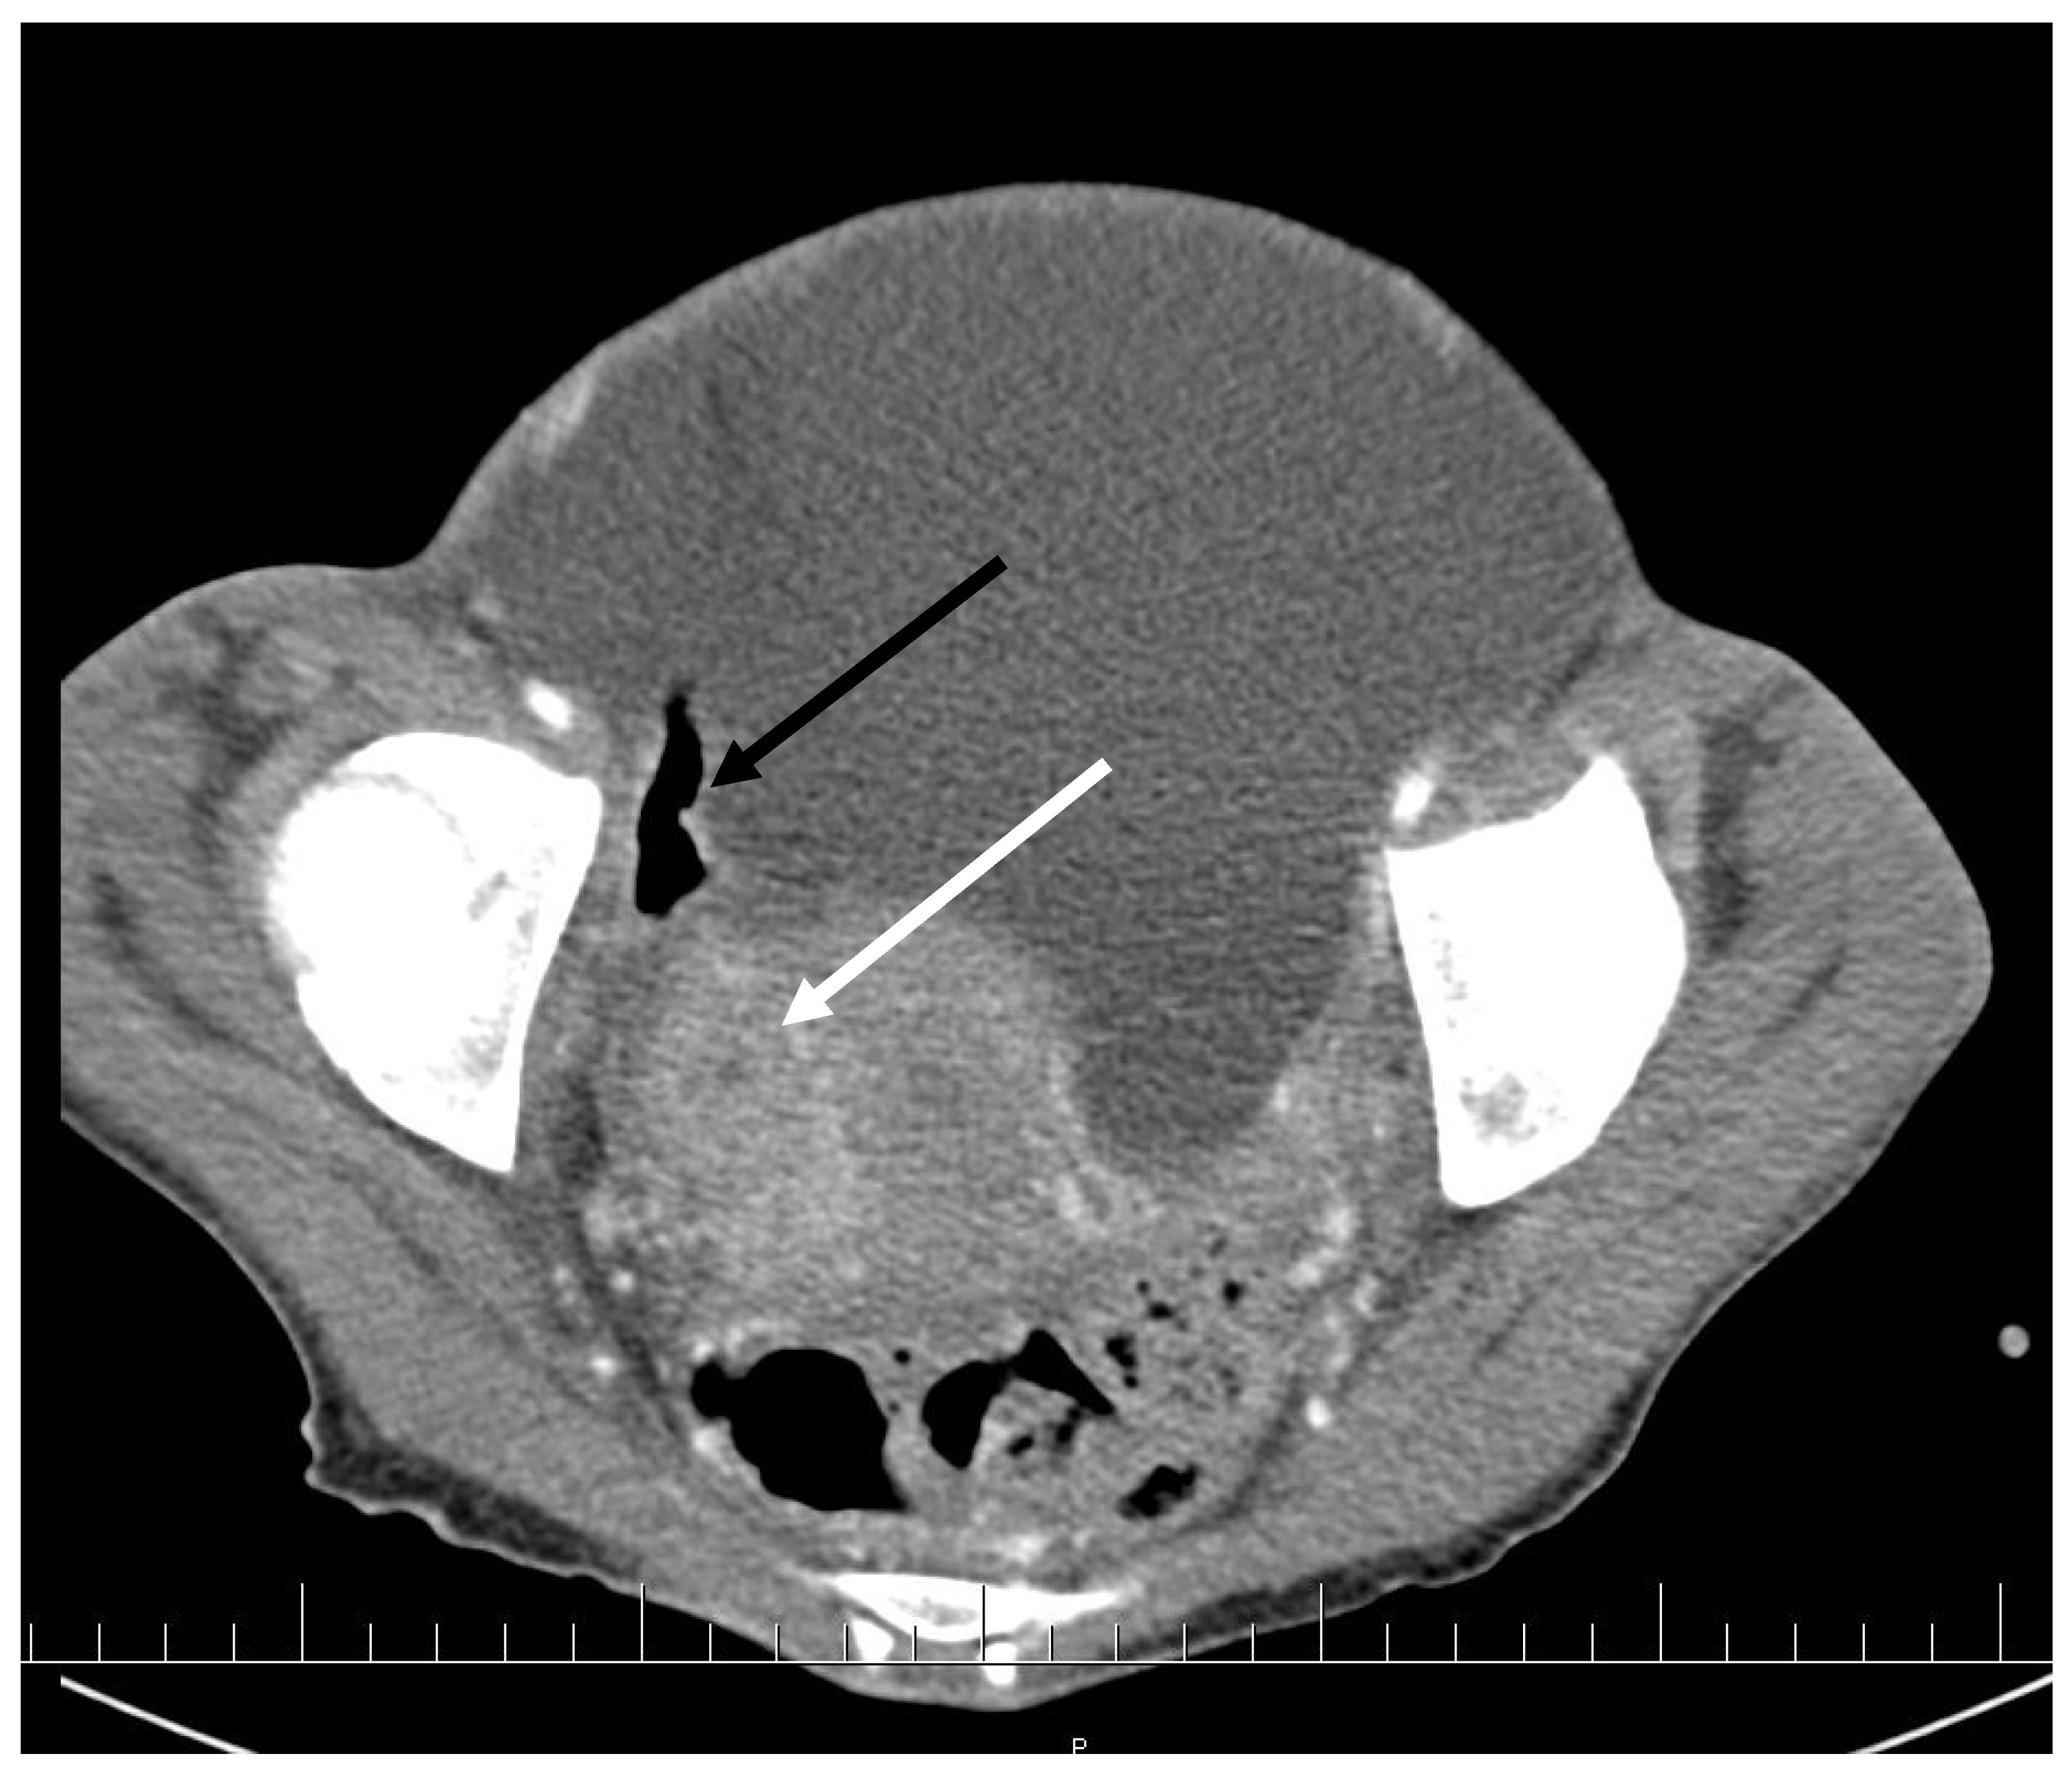

CT scan showed ascites, an enlarged right ovary with a parauterine non-homogenous mass 8 × 5 cm in size containing gas, bilateral hydronephrosis, ischaemic foci in spleen, multiple bilateral tiny nodules in the lungs with mainly subpleural distribution resembling miliary tuberculosis or multiple emboli, multiple liver lesions described as signs of Budd–Chiari’s syndrome due to the inferior vena cava thrombosis, and right hepatic vein thrombosis (Figure 1 and Figure 2).

Figure 1. Pelvic CT scan shows ascites, enlarged right ovary (white arrow) and a gas-containing non-homogenous mass adhering to the uterus (black arrow).